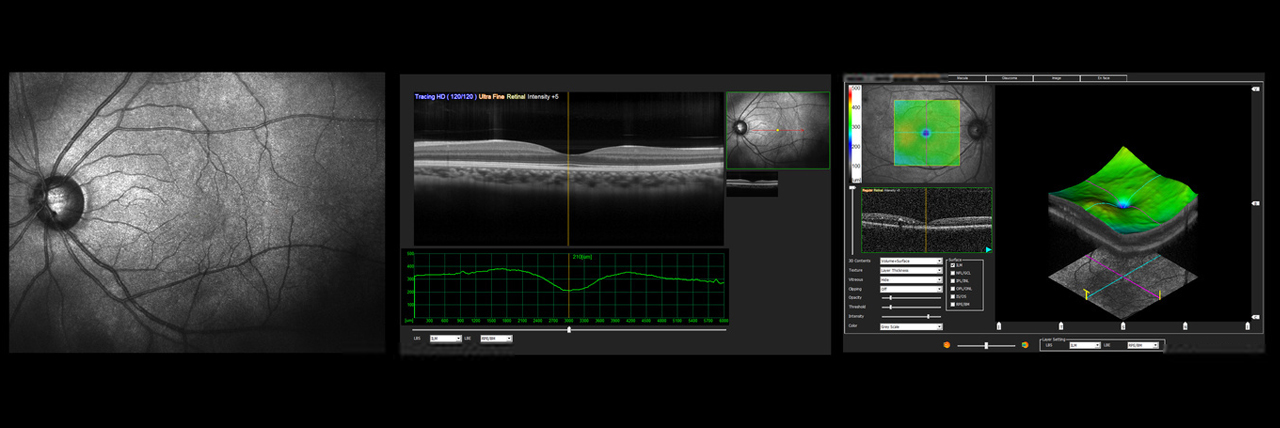

Netzhaut

Optische Kohärenztomographie (OCT), Fluoreszenzangiographie,

Fundus-Autofluoreszenz,

Fundus-Fotographie